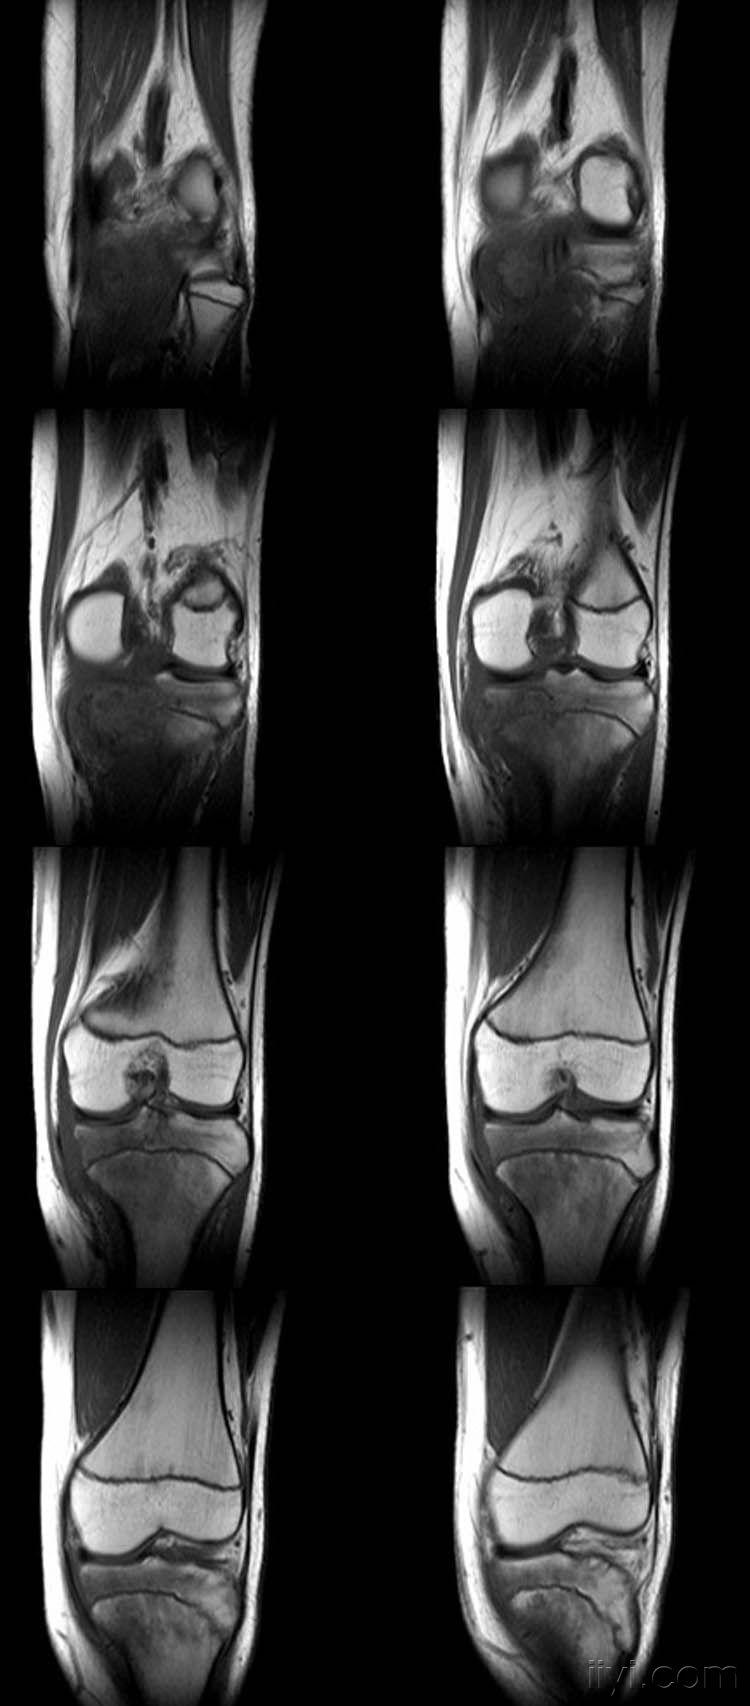

女,14岁,膝关节外伤后疼痛4月余。

向老师学习,恶性肿瘤可能,骨肉瘤?